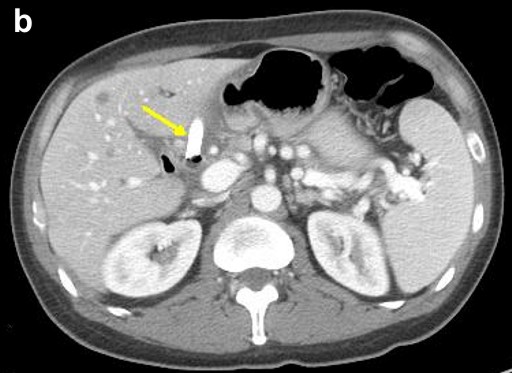

Thus, EUS-guided transduodenal biliary drainage (EUSBD) was performed. A linear array echoendoscope (GF-UCT140, Olympus America, Center Valley, PA, USA) was placed in the duodenal bulb allowing visualization of a dilated common bile duct (Figure 1). A 19-gauge FNA needle (Wilson-Cook Endoscopy, Winston-Salem, NC, USA) was used to perform a transduodenal puncture of the common bile duct through the proximal end of the duodenal stent. Bile was aspirated and a cholangiogram demonstrated good filling of the right and left duct systems with no evidence of a stricture proximal to the puncture site (Figure 2). Under fluoroscopy, a 0.035-inch straight guidewire (Jagwire, Boston Scientific Corporation, Natick, MA, USA) was passed into the biliary tree and directed toward the hilum. The FNA needle was exchanged for a biliary dilating balloon (Hurricane RX, Boston Scientific Corporation, Natick, MA, USA). The choledochoduodenostomy tract was dilated to 6 mm. A 10x60 mm fully covered self-expanding metal biliary stent (Wallfex®, Boston Scientific Corporation, Natick, MA, USA) was placed over the guidewire and deployed under fluoroscopy. One cm of the stent was left protruding into the duodenal bulb through the mesh at the proximal end of the duodenal stent (Figure 3). Good bile and contrast efflux was seen. The final fluoroscopic image did not demonstrate a bile leak (Figure 4). Post-procedure CT imaging demonstrated good positioning of the biliary stent and no evidence of a bile leak (Figure 5).

Figure 5. Post-procedure CT demonstrating: a. juxtaposition of metal biliary (yellow arrow) and duodenal (green arrow) stents with no evidence of a bile leak; b. fully covered metal biliary stent (yellow arrow) terminating in the common bile duct; c. no evidence of pelvic ascites to suggest a bile leak. |